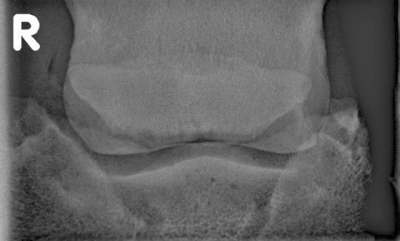

Zubildung am oberen und unteren Strahlbeinrand, krankhaft veränderte Gefäßkanäle